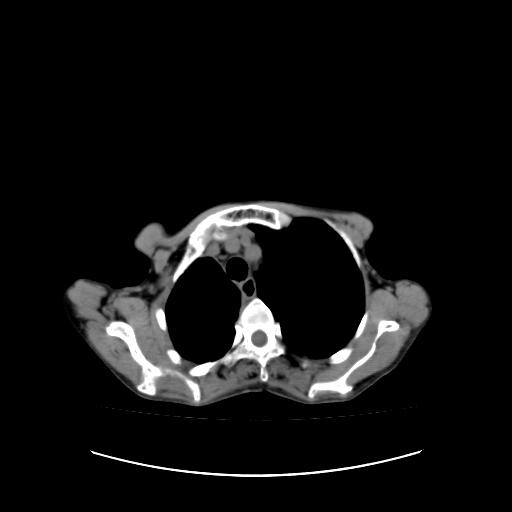

标题: CT16930:女 59 胸痛6个月 胸水脱落细胞学见瘤细胞 [打印本页]

标题: CT16930:女 59 胸痛6个月 胸水脱落细胞学见瘤细胞

右侧胸膜增厚,局部呈结节状增厚,右侧胸腔少量积液。双肺未见确切肿块影。纵隔未见淋巴结肿大。气管、支气管通畅。考虑右侧胸膜间皮瘤(恶性?)可能性大。不除外癌性胸膜炎。

右侧胸廓塌陷,右侧胸膜广泛增厚并见多发胸膜结节,右侧少量胸腔积液并包裹。

右侧广泛胸膜增厚,局部呈结节状增厚,右侧胸腔少量积液。双肺未见确切肿块影。纵隔未见淋巴结肿大。气管、支气管通畅。考虑右侧胸膜间皮瘤(恶性?)可能性大。支持!